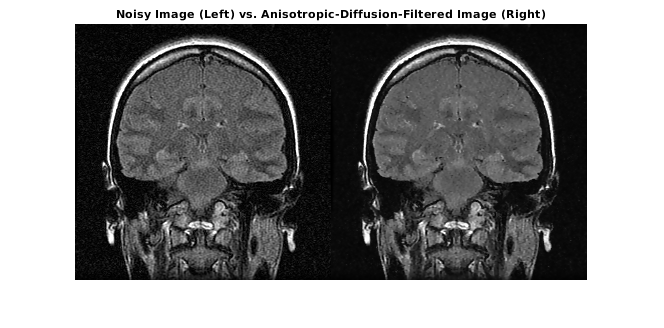

Загрузите шумный 3-D полутоновый объем MRI.

load mristackВыполните осведомленное о ребре шумоподавление на объеме с помощью анизотропной диффузии. Чтобы предотвратить сверхсглаживание низкоконтрастных функций в мозгу, сократите число итераций от номера по умолчанию, 5. Компромисс - то, что меньше шума удалено.

diffusedImage = imdiffusefilt(mristack,'NumberOfIterations',3);Чтобы сравнить шумное изображение и отфильтрованное изображение подробно, отобразите десятый срез обоих.

imshowpair(mristack(:,:,10),diffusedImage(:,:,10),'montage') title('Noisy Image (Left) vs. Anisotropic-Diffusion-Filtered Image (Right)')

Вычислите счет Средства анализа качества изображения естественности (NIQE), усредненный по всем срезам в объеме. Счет NIQE обеспечивает количественные показатели качества изображения, которое не требует ссылочного изображения. Понизьтесь баллы NIQE отражают лучшее перцепционное качество изображения.

The NIQE score of the noisy volume is 5.7794.

The NIQE score using anisotropic diffusion is 4.1391.

Счет NIQE сопоставим с наблюдением за уменьшаемым шумом в отфильтрованном изображении.